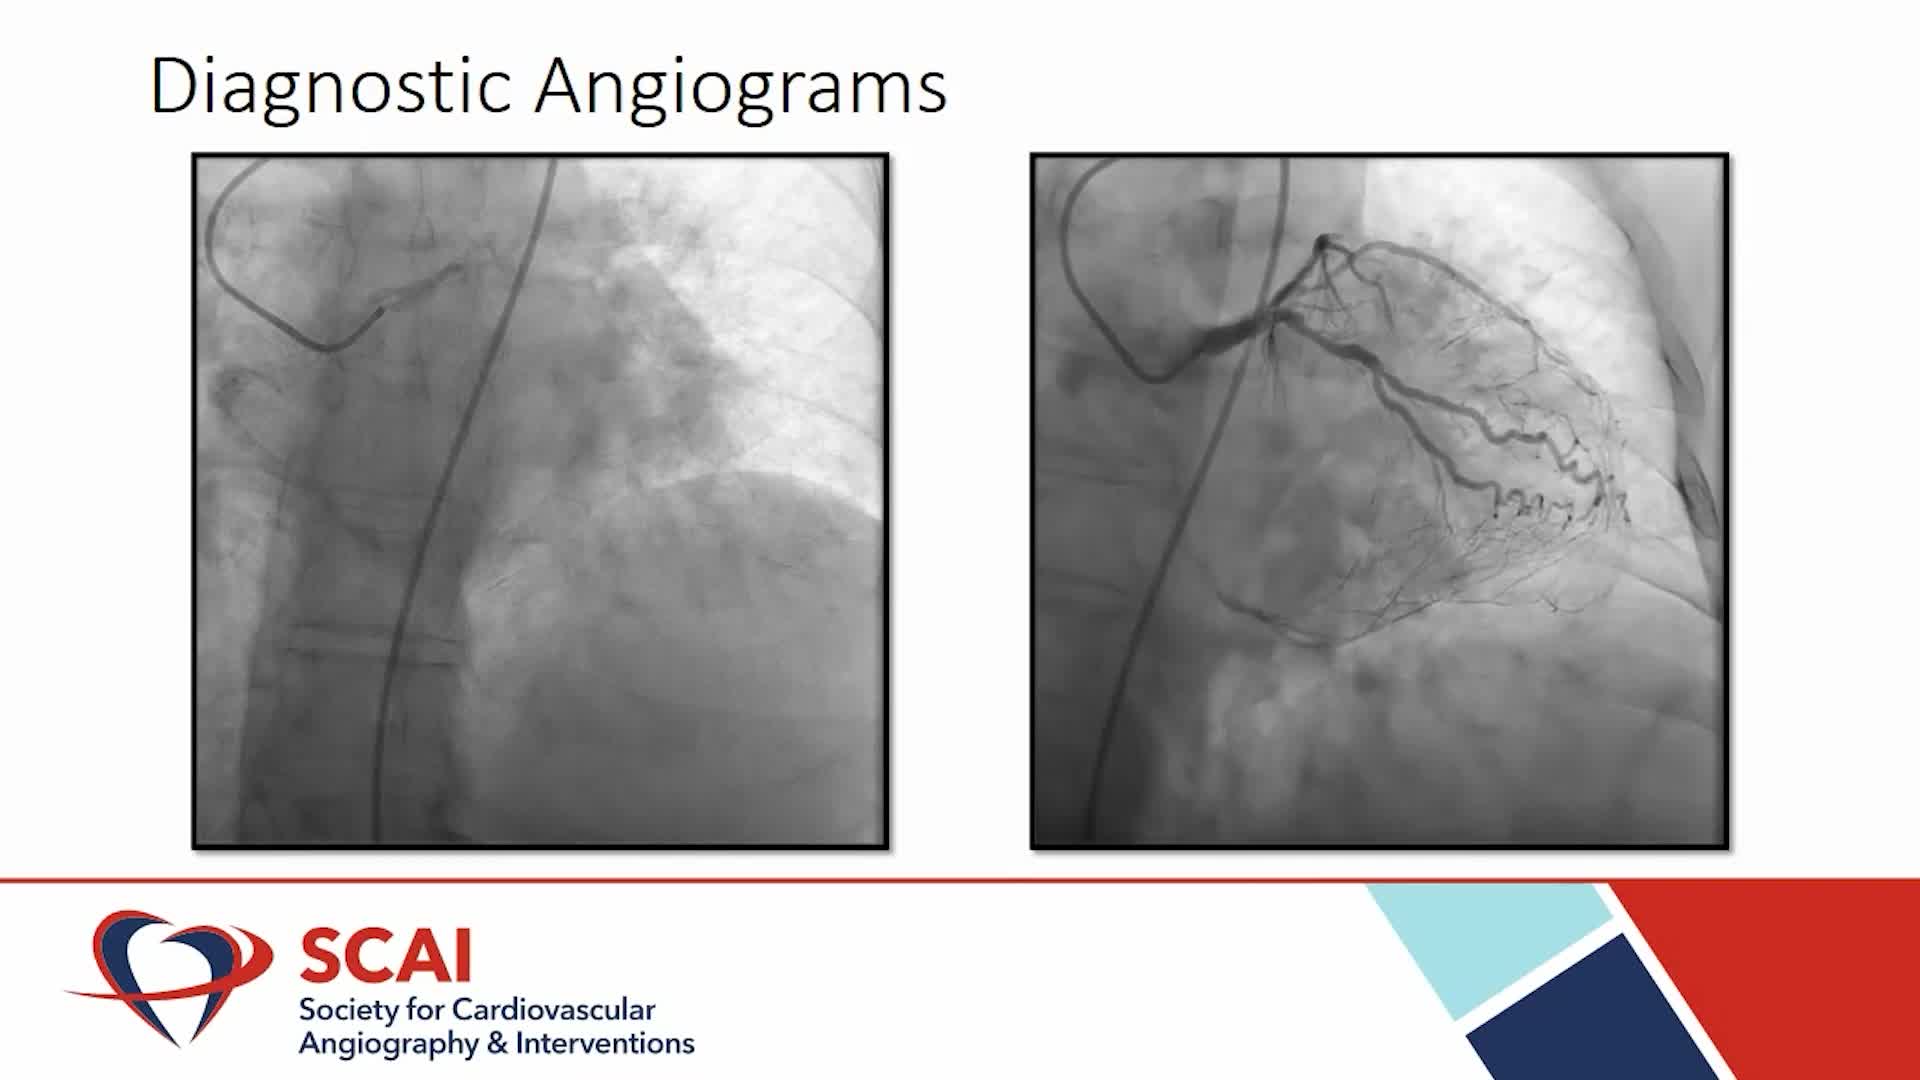

Real-World EU Experience: Coronary IVL Across Different Calcium Morphologies from TCT 2022

Shockwave IVL Coronary Real-World Cases, Outcomes & Algorithms: An InCathLab Webinar